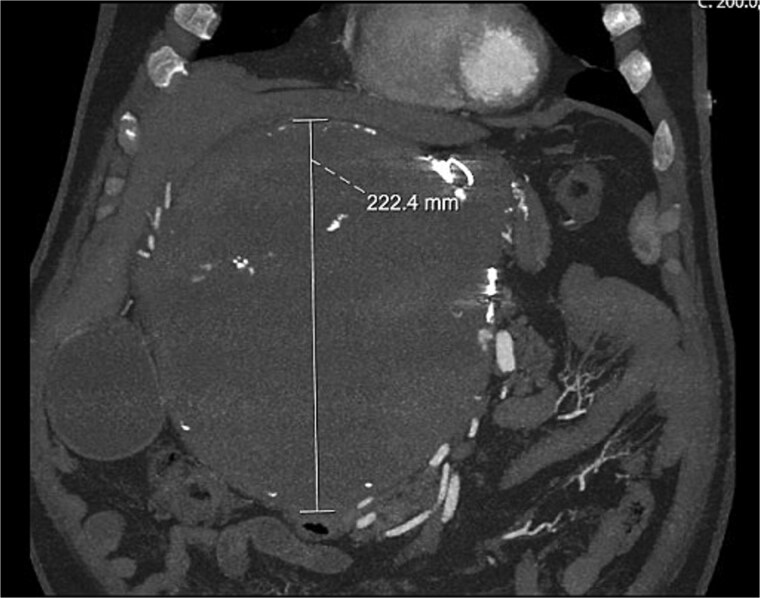

肝动脉动脉瘤(HAAs)是一种罕见的血管病变,如果不治疗,有很大的破裂风险和高死亡率。我们报告了一位59岁的男性,他在已知HAA栓塞失败10年后再次出现严重的胸腹疼痛。影像学显示巨大病变伴广泛的局部肿块效应,最终需要复杂的多脏器切除和血管重建才能达到明确的治疗。

Hepatic artery aneurysms (HAAs) are rare vascular lesions with significant risk of rupture and high mortality if untreated. We report a 59-year-old male who re-presented with severe chest and abdominal pain 10 years after failed embolization of a known HAA. Imaging revealed a massive lesion with extensive local mass effect, ultimately requiring complex multivisceral resection and vascular reconstruction to achieve definitive management.